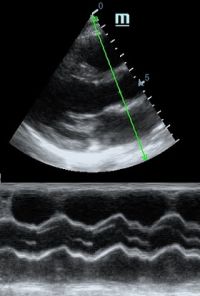

Но как же провести стандартные измерения в М-режиме, если мы его не использовали? На помощь приходит функция Free Xros M – анатомический М-режим. Имея записанную в память прибора видео петлю, мы можем провести линию М-режима в любом месте, при этом корректируя изначально не оптимальный угол.

Возможности применения функции многогранны: от измерения толщины стенок левого желудочка, движения створок митрального клапана и кооптации нижней полой вены до оценки сократимости миокарда как глобально, так и по сегментам.

TAPSE - показатель амплитуды движения латеральной части кольца трикуспидального клапана, позволяет количественно и быстро оценить систолическую функцию правого желудочка, норма которого составляет более 17 мм. Главным условием является проведение линии М-режима параллельно стенке правого желудочка в апикальном четырех камерном сечении, что легко достигается при Free Xros.

MAPSE - амплитуда движения латерального кольца митрального клапана, позволяет рассчитать фракцию выброса по формуле EF = 4.8 × MAPSE (mm) + 5.8, очень быстрый и гораздо более точный («прародитель Strain») метод чем широко распространенный метод Teicholtz. В современных приборах можно легко добавить свою формулу при отсутствии ее в стандартном калькуляторе. Главным условием является проведение линии М-режима параллельно стенке левого желудочка в апикальном четырехкамерном сечении, что легко достигается при использовании функции Free Xros.